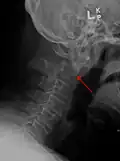

-

A fracture of the base of the dens as seen on plain X-ray -

Type 3 odontoid fracture -

Type 2 dens fracture